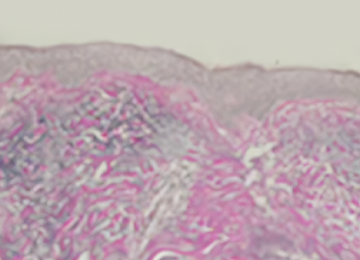

세계적인 레이저 회사인 이스라엘의 ALMA사의 신개념 첨단 의료 장비로

공기 중의 질소와 고주파 에너지가 만나는 순간 발생하는

플라즈마라는 불꽃을 이용해 피부 문제를 개선합니다.

피부의 얕은 층부터 깊은 층까지 침투가 가능해 모공, 미백, 탄력,

흉터, 피부 톤, 피부 결, 여드름을 안전하게 치료합니다.